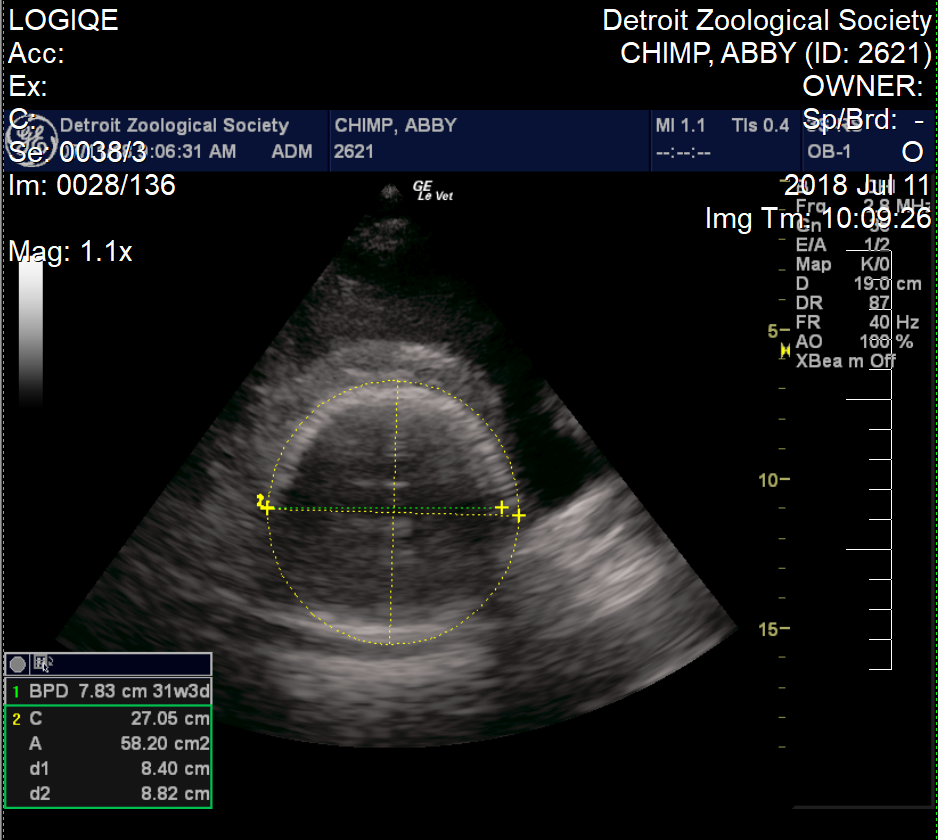

Abby was a cooperative patient and always appeared excited to see us. She would prop herself on a ledge and eat peanuts during each exam, allowing the peanut shells to pile up on her growing belly. There are limits to the ways we can position the probe, and we were not always able to get every measurement at every visit. In the early months, we were able to measure the length of the fetus from the crown to the rump; as the baby grew, we measured the circumference of the head and abdomen and length of the long bones, including the femur and humerus. We were also able to see the position of the fetus and measure the heart rate. With each exam, we added data to our growth charts, and were pleased to see steady growth and development. We also became increasingly confident that the baby was a girl.

Abby is the third chimpanzee mom that has allowed us to conduct obstetrical ultrasounds, and since 2008 we have been able to collect measurements from three pregnancies, including youngsters Ajua and Akira. Using these measurements and data from two scientific publications, we were able to make a solid prediction of Abby’s due date – July 14, the date of the first annual World Chimpanzee Day! As this date approached, animal care staff began round-the-clock checks to look for signs of labor. Just three days before the due date, we performed a final ultrasound exam. We were pleased to see that the baby was still growing according to expectations. We could see her face and watch her open and close her mouth and wiggle her arms and legs. Most importantly, we could see that the baby had a strong heartbeat and was positioned with her head down, which is the correct position for a normal delivery.